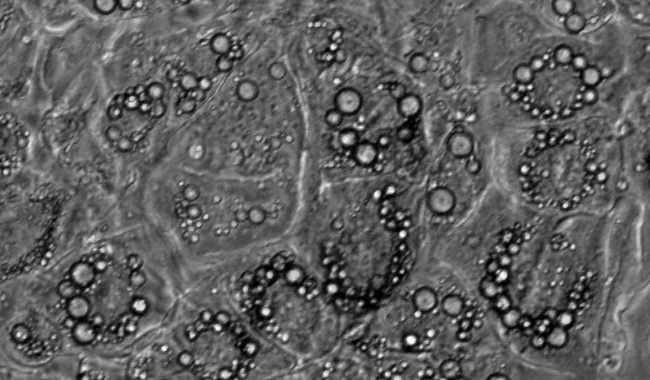

脂滴計數(shù)圖像分析

脂滴是調(diào)節(jié)中性脂質(zhì)儲存的基礎(chǔ),可以根據(jù)脂滴研究代謝的需求。但它們不僅是能量庫,因為這種動態(tài)的細(xì)胞器是許多生物過程的一部分,如細(xì)胞能量平衡和脂質(zhì)代謝。脂滴法在代謝性疾病的研究,如肥胖、糖尿病和動脈粥樣硬化有重要的作用。

脂滴個數(shù)

脂滴覆蓋面積

平均覆蓋面積

區(qū)間分布

單個細(xì)胞的脂滴個數(shù)和覆蓋面積